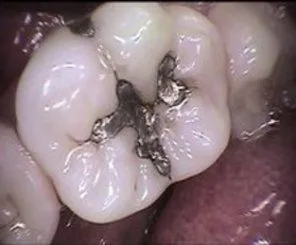

Cosmetic Composite Filling

Before

After